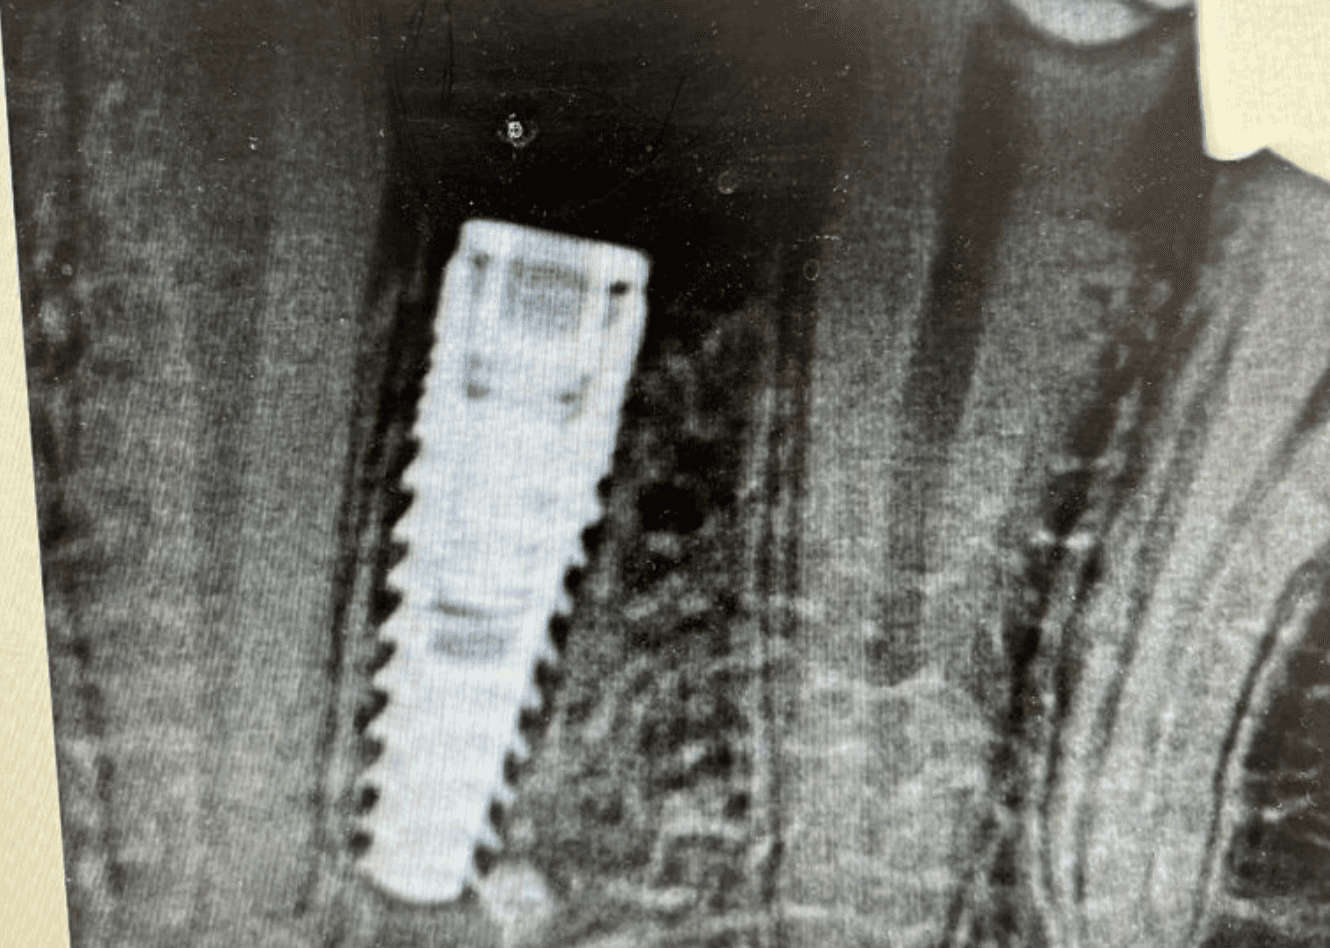

Too Close For Comfort?

Complications